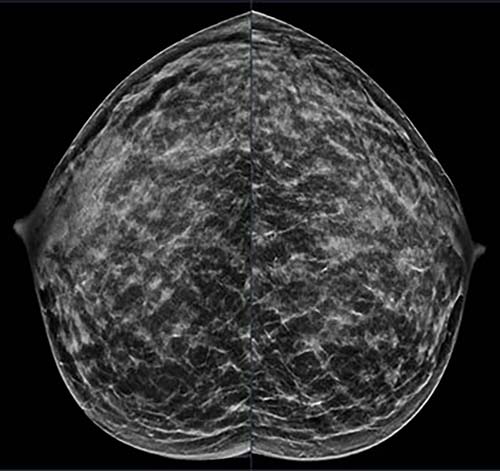

Figure 1. 40-year-old patient presents for routine screening. Family history of paternal grandmother age 55. Extremely dense breast tissue is noted on mammography right and left craniocaudal (taken from the top of the breast) view.